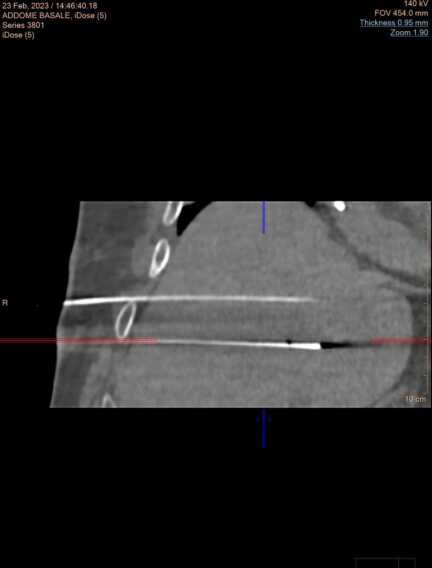

La procedura, che tecnicamente si chiama di elettroporazione irreversibile con tecnica stereotassica robotizzata Tc, è una nuova tecnica di distruzione dei tumori collocati in sede non diversamente trattabili perché vicini a strutture vascolari o biliari ed è eseguita con l’ausilio della tac e di un robot.

Questa procedura è stata impiegata su un paziente di 68 anni, già operato per un voluminoso tumore del fegato, che aveva sviluppato una recidiva maligna non suscettibile di intervento chirurgico né di trattamenti ablativi termici proprio per la collocazione “critica” dovuta alla vicinanza di strutture vascolari.

Il trattamento è stato eseguito con successo dal direttore dell’Unità operativa Diagnostica e Radiologia interventistica dell’Irccs “De Bellis”, dottor Fabio Fucilli, e non sono comparse complicanze peri-procedurali. È stato il risultato di un grande lavoro di equipe multidisciplinare (radiologi interventisti, anestesisti, tecnici radiologi e personale infermieristico specializzato) di elevato profilo e competenza che opera quotidianamente in modo integrato.